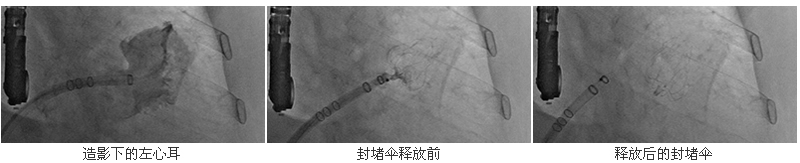

经皮左心耳封堵术是近年来发展起来的一种预防房颤患者血栓栓塞事件的创新治疗术式。它适应房颤合并有下列危险因素之一者,包括:高龄、高血压、冠心病、糖尿病、心衰、中风的患者,尤其是既往容易出血、有出血史的患者,更不适合终身药物抗凝治疗。该手术无切口,仅需在股静脉穿刺一个针眼,通过导管将一左心耳封堵器安置在左心耳开口部位,达到封闭左心耳,封预防左心耳内血栓脱落引起的血栓栓塞,从而避免缺血性脑卒中和全身性栓塞的发生。左心耳封堵术能消除患者对于长期抗凝治疗的依赖,避免了患者因抗凝药物所产生的不耐受、出血事件和依从性等问题,也为对抗凝药物具有禁忌证的患者带来了新希望。

6月28日,在德国Bad Berka心脏中心的副院长、著名德籍华裔心血管病专家余江涛教授指导下,我院心血管内科副主任柴大军副教授带领心血管介入诊疗团队、心脏超声团队及麻醉科团队多科协作,经过5个多小时的奋战,先后连续为陈依姆等3名患者成功施行房颤左心耳介入封堵术,使他们从长期服用华法令的痛苦中得到了解脱。由于采用微创技术,仅需在患者股静脉穿刺一个针眼,术后当日患者即可起床活动,手术并发症少,而且手术时间较短,对于老年人或者不能耐受外科手术的患者来说也很安全。目前接受左心耳封堵术的3名患者术后恢复情况都十分理想,均已康复出院。该项手术的成功完成不仅填补了我院在该领域的技术空白,也使我院成为目前福建省完成该项手术例数最多的单位,体现了我院不同学科团队间的团结协作、锐意进取和开拓创新精神。